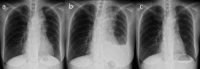

Pseudoprogression, a transient radiographic flare caused by immune infiltration, is common after immune-checkpoint inhibitors but has not been reported with tarlatamab, a bispecific T-cell engager approved for third-line small-cell lung cancer (SCLC). A 57-year-old woman with extensive-stage SCLC and syndrome of inappropriate antidiuretic hormone secretion (SIADH) received tarlatamab. Within hours, she developed bone pain; Day 7 imaging showed marked tumour swelling and pleural effusion despite negative cytology and rising serum sodium. Therapy continued. By Day 13, computed tomography demonstrated regression of thoracic and hepatic lesions and falling pro-gastrin-releasing peptide (pro-GRP). Early pseudoprogression and paraneoplastic biomarker improvement may predict efficacy.